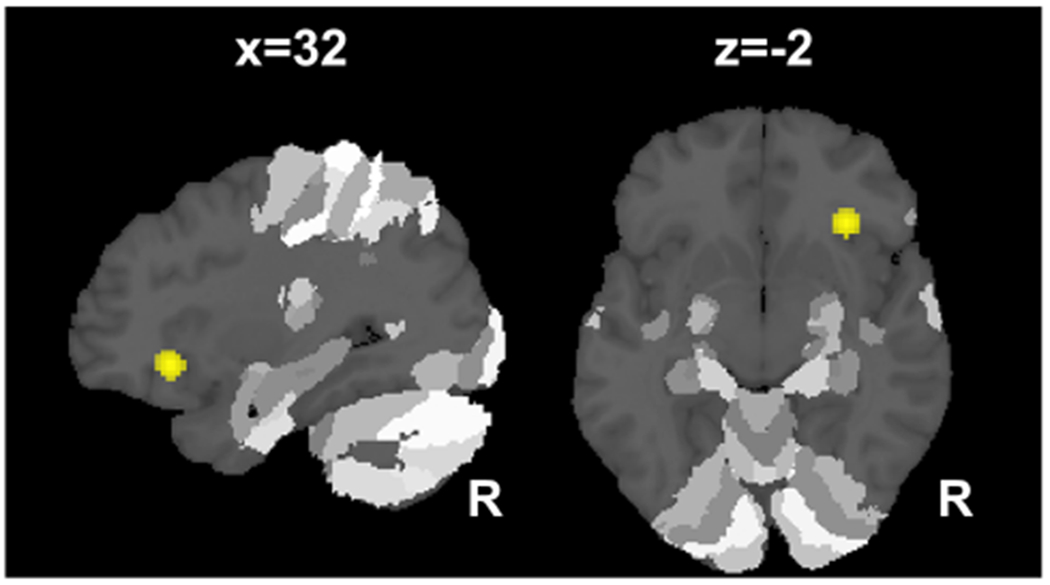

During verbal retrieval, MCI patients showed decreased activation in the right anterior insula (Fig. 2), while attenuated activation was observed in the left anterior hippocampus (CA1, CA4) extending to the left fusiform gyrus (Fig. 1b) for the image stimuli subgroup.

Fig. 2.

Decreased insula and inferior frontal gyrus activation during verbal retrieval tasks in patients with mild cognitive impairment. Patients with mild cognitive impairment showed less activation during verbal retrieval in the right anterior insula extending to the inferior frontal gyrus when compared to controls. All clusters are family-wise error cluster corrected at p < 0.05. R right hemisphere, x, z in Montreal Neurological Institute (MNI) coordinates